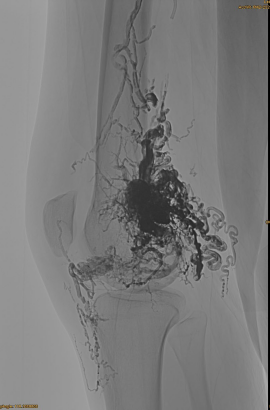

DSA iniziale:

Risultato finale:

Difficilmente nessun deflusso venoso:

Fase tardiva, un altro embo necessario, ma molto meglio: